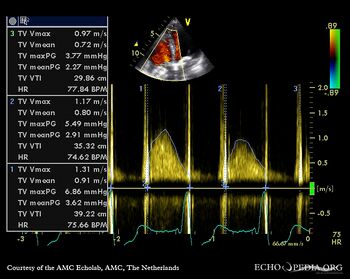

| Continuous-wave Doppler signal of transtricuspid flow | PSAX: pulmonary valve prosthesis |